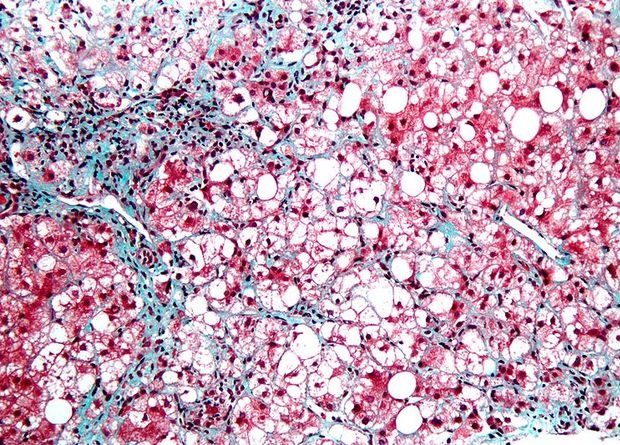

Американские ученые впервые использовали Т-лимфоциты для борьбы с сенесцентными клетками, появление которых сопровождает старение тканей. Для этого они воспользовались технологией CAR-T: модифицировали иммунные клетки так, чтобы они распознавали распространенный на поверхности сенесцентных клеток белок. Метод оказался эффективен не только in vitro, но и in vivo, и улучшил состояние мышей при фиброзе легких и печени, а также при стеатогепатите. Кроме того, в минимальных дозах он не вызвал никаких побочных эффектов. Исследование опубликовано в журнале Nature.

Поэтому в качестве сенолитиков — препаратов, которые призваны очистить ткань от старых клеток — тестируют некоторые противоопухолевые лекарства, так как они действуют избирательно на клетки с заблокированным апоптозом. В отдельных экспериментах сенолитики уже показали свою способность продлевать жизнь мышам и улучшать (правда, пока незначительно) состояние людей с разными возрастными заболеваниями, например, воспалением суставом, фиброзом легких и диабетом.